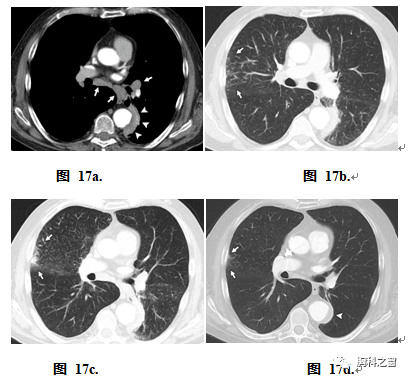

Hirano等(74)发现13%的自身免疫性胰腺炎患者存在肺部受累。已明确的IgG4相关性肺部疾病的四种主要类型:(a)以实性结节或肿块样病变为特征型,(b)以圆形磨玻璃阴影为特征型,(c)肺泡间质性病变型,以及(d)支气管血管性病变型(75)。小结节和肿块样病变常被误诊为肺癌(图17)。偶尔,组织学诊断为炎性假瘤。部分肺部炎性假瘤伴有淋巴浆细胞浸润、纤维化、阻塞性静脉炎和IgG4阳性浆细胞浸润,属于IgG4-RD范畴(76)。当IgG4相关肺部疾病在CT上表现为圆形毛玻璃样阴影时,影像学可能诊断为支气管肺泡癌。肺泡间质性病变类型是毛玻璃影和蜂窝状影的混合物,须与非特异性间质性肺炎相鉴别。在支气管血管性病变类型的IgG4相关性肺部疾病中,可见小叶间隔增厚,且常伴有肺门和/或纵隔淋巴结病变,可与结节病相似(75)。文献报道可见脏层或壁层胸膜增厚,有时累及胸膜下肺实质(图18)(76)。

图17:男,76岁,IgG4相关性肺部病变。患者无症状,但血清IgG4浓度(856 mg/dL)升高,肾脏受累的影像学表现(见图14)。(a)轴位CT增强图示纵隔和左肺门淋巴结病变(箭)以及主动脉旁肿块(箭头)。(b,c)不同层面轴位CT图示右肺上叶外周小叶间隔增厚,以及一小部分胸膜下肺泡(气腔)疾病(b–d中箭头)。推测性诊断为IgG4-RD,并进行皮质类固醇治疗。(d)治疗后轴位CT图示,包括主动脉旁肿块(箭头)在内的所有病变均已缩小。(案例由西班牙巴塞罗那医学博士Eva Castañer提供。)